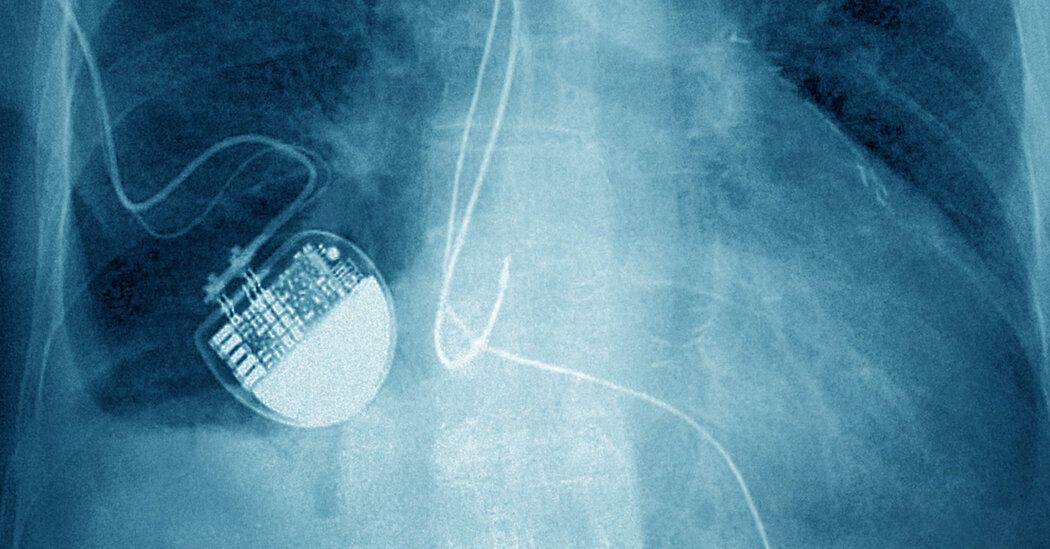

Like about three million Americans, Nancy Guthrie, the 84-year-old mother of NBC News anchor Savannah Guthrie, has a pacemaker implanted in her chest.

A pacemaker constantly records a person's heart rate and uses that data to prevent it from dropping too low. If a person's lowest heart rate is set at 50, for example, the pacemaker will send painless electronic pulses when the rate drops to increase it again (unlike an implanted defibrillator, which shocks a stopped heart).

Pacemakers constantly record data, but do not provide information about the patient's location, said Dr. Roderick Tung, director of the cardiac electrophysiology program at Banner University Medical Center Phoenix in Arizona.

A large majority of patients use remote monitoring, which involves a device that is typically placed on a nightstand. In some cases, this is an application on a smartphone. The monitor checks the data stored in the pacemaker throughout the day. Investigators did not say which company made Guthrie's device, or whether it uses that tracking method.

Dr. Kenneth Stein, global medical director at Boston Scientific, which makes pacemakers, explained that periodically, a remote monitoring instrument “wakes up” and transmits data, often at night when the patient is sleeping.

This data indicates whether the battery is in good condition and whether the pacemaker is working as it should. The device also transmits alerts if something is wrong with the patient's heart.

For pacemaker data to be sent to the monitor, the person must be nearby, typically no more than 10 feet away, Dr. Tung said.